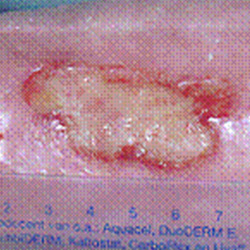

Before and After